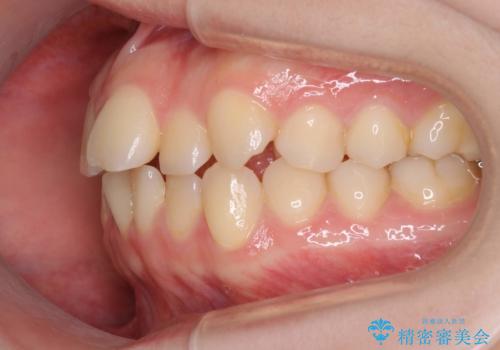

インビザラインによるガタつきの矯正治療 シンプル・短期間

- 20代女性

- invisalign full

- 1年6ヶ月

- 非抜歯、IPR+拡大によるマウスピース矯正を計画した。

一見前歯のガタつきだけのように見えても、そのガタつきの根本的な原因が奥歯の位置であったりすると、マウスピースの枚数がそれなりに多くなり、治療に時間がかかることもあります。